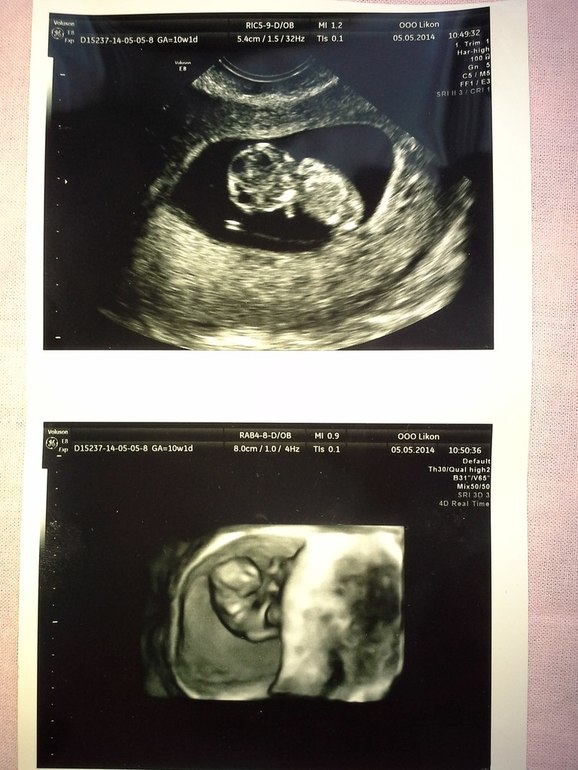

В 9 недель решила пойти на УЗИ...

Девочки, только там я успокоилась...ВСЁ ХОРОШО=))) МНЕ ЕГО ПОКАЗАЛИ

Я РЕВЕЛА ЧАС НАВЕРНОЕ ОТ СЧАСЬЯ... МОЙ МАЛЕНЬКИЙ ИНОПЛАНЕТЯНЧИК=)) МОЁ СОКРОВИЩЕ!!!

Я РЕВЕЛА ЧАС НАВЕРНОЕ ОТ СЧАСЬЯ... МОЙ МАЛЕНЬКИЙ ИНОПЛАНЕТЯНЧИК=)) МОЁ СОКРОВИЩЕ!!! И ТЕПЕРЬ Я УВЕРЕННА, ЧТО ВСЁ БУДЕТ ХОРОШО!!!